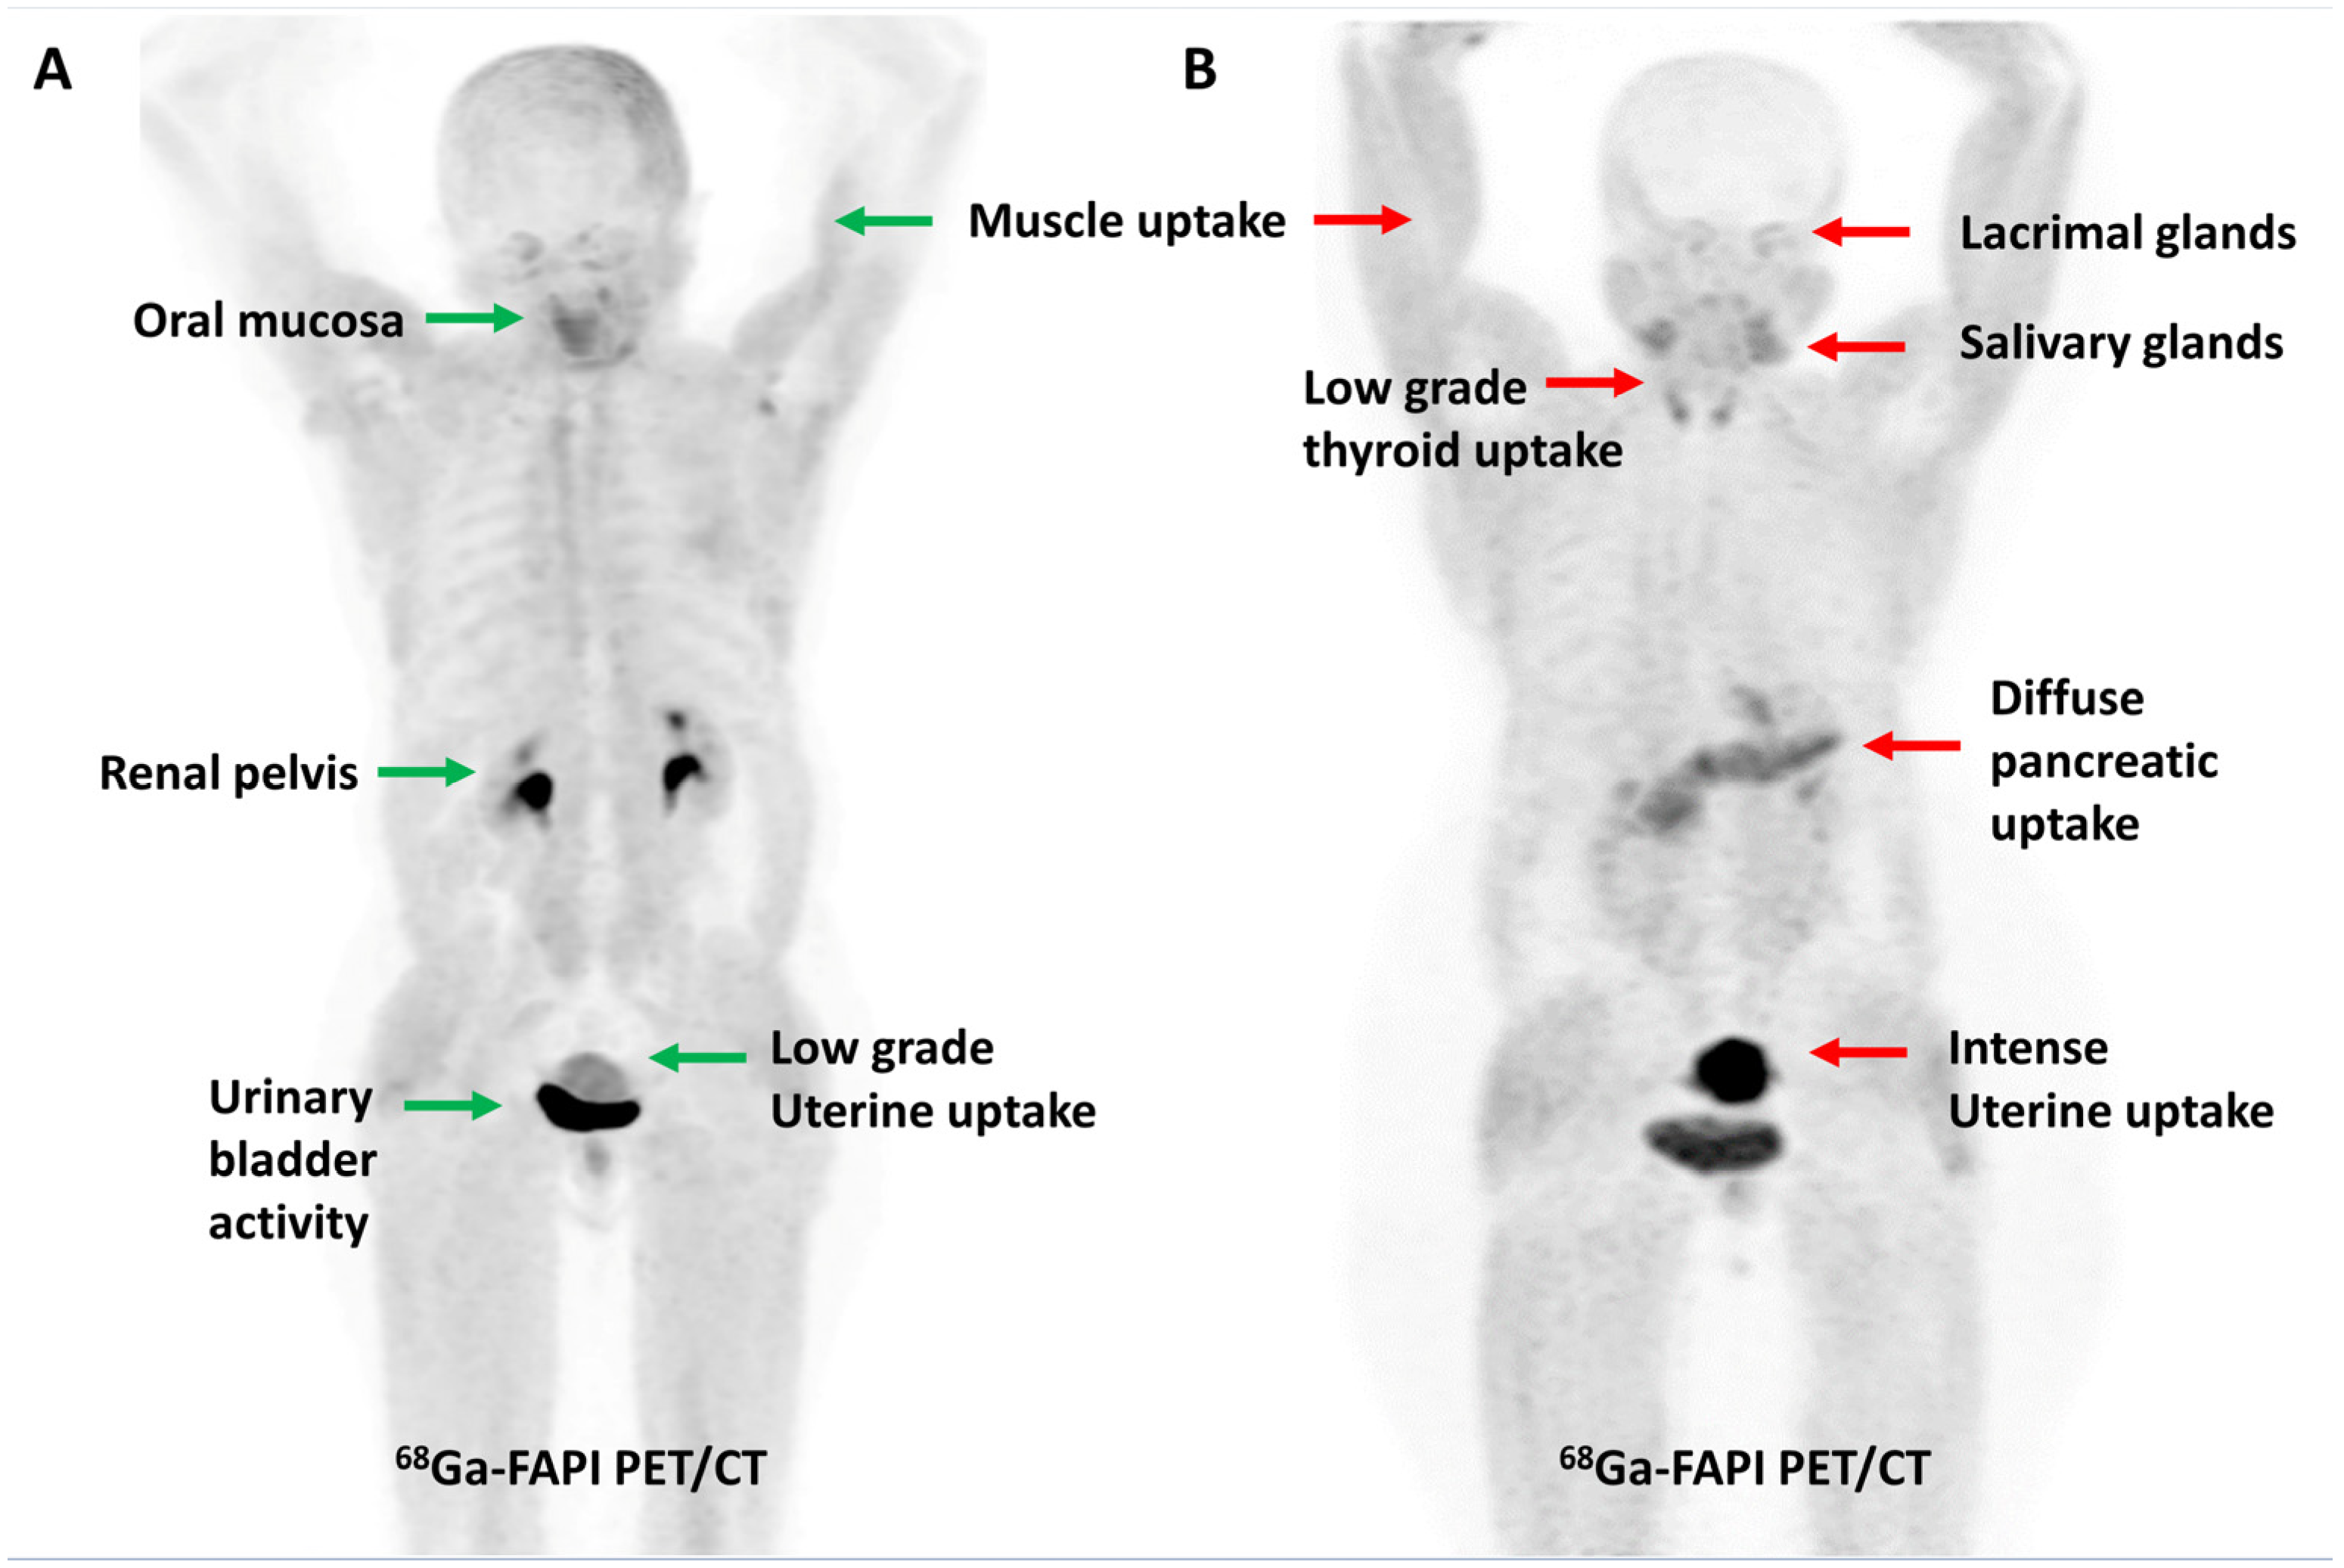

FAP expression has been reported in over 90% of epithelial neoplasms [43]. As tumor lesions grow, they need a supporting stroma for their sustenance. Given that stroma volume can be larger than the volume of neoplastic cells, FAP-targeted PET imaging may be more sensitive than FDG PET imaging for detecting small lesions or for lesions with negligible or heterogeneous glucose metabolism. From a feasibility point of view, the ability to acquire scans as early as 10 min post-injection, lack of fasting requirements, or the need to withhold insulin/steroids makes FAPI PET imaging easier to perform, particularly in the diabetic and pediatric populations. The physiological biodistribution of FAPI tracers typically includes the uterus, spleen, lungs, heart, pancreas, oral mucosa, salivary glands, thyroid, and liver, with predominant urinary excretion, as shown in Figure 1 [44]. Radiation dosimetry studies have found that 68Ga-labeled FAPI tracers (FAPI-02, FAPI-04 and FAPI-46) typically result in a whole-body effective dose ranging from 1.5 to 4mSv (per ~200 MBq of tracer), which is comparable to or lower than the commonly used tracers such as FDG, [68Ga]Ga-PSMA-11, and [68Ga]Ga-DOTATATE. A lower average effective whole-body dose has been reported with [68Ga]Ga-FAPI-46 than with [68Ga]Ga-FAPI-04 (7.80 × 10−3 vs. 1.27 − 1.64 × 10−2 mSv/MBq, respectively). The urinary bladder wall has consistently been reported as the organ with the highest absorbed dose for various 68Ga-labeled FAPI tracers. For [68Ga]Ga-FAPI-04, Wang et al. reported that the organ with the highest mean absorbed dose was the urinary bladder (1.45 × 10−1 mGy/MBq), followed by uterus, kidneys, lungs, spleen, heart wall, and pancreas, in descending order [45,46,47,48,49,50].

Figure 1.

Maximum intensity projection PET images demonstrating the physiological distribution of [68Ga]Ga-FAPI-04 in two representative cases. Low-grade uterine uptake (green arrow) noted in a 55-year-old post-menopausal woman (A) is in stark contrast to the intense uterine uptake (red arrow) noted in a 42-year-old premenopausal woman (B).